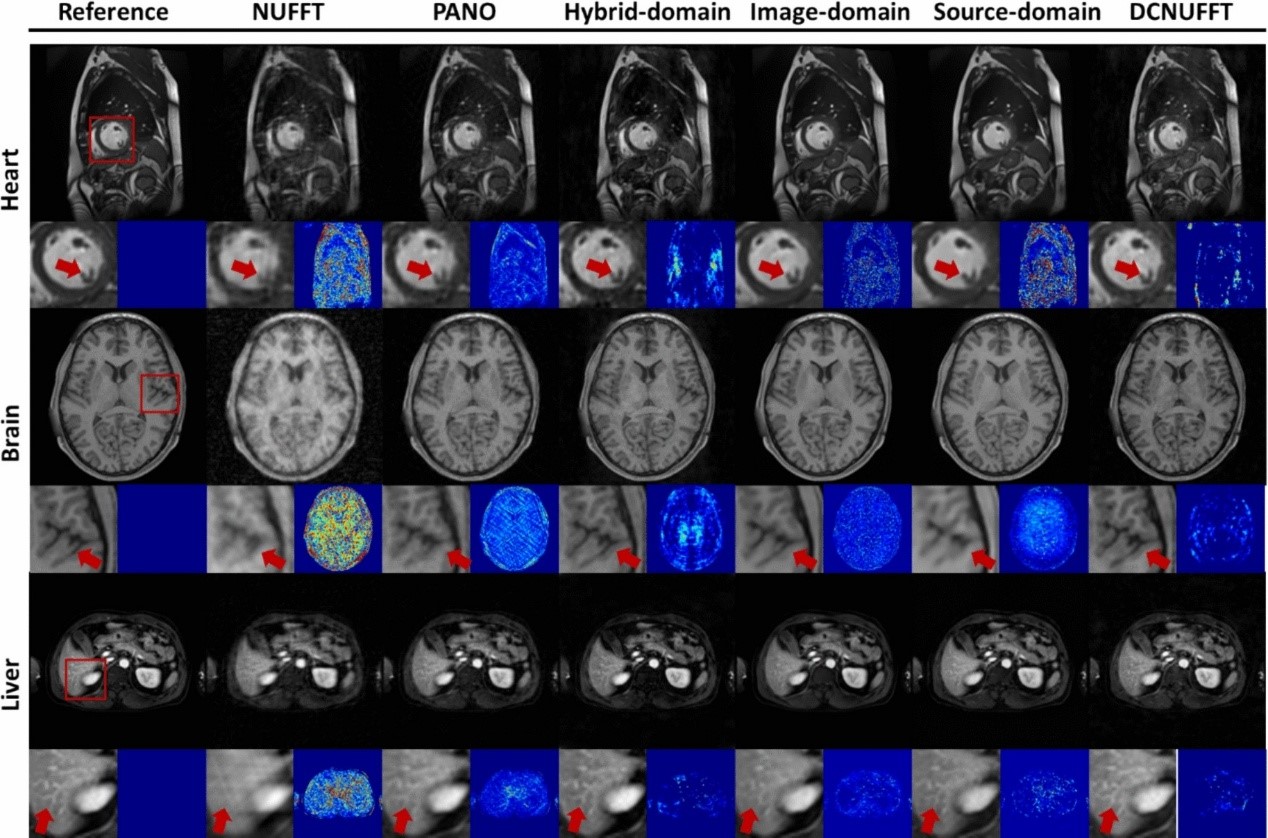

在心脏、大脑和肝脏的MRI数据上进行的回顾性重建实验中(采样率R=4),DCNUFFT展现出卓越性能。如图3所示,传统反NUFFT方法产生明显伪影与高噪声;基于Patch的迭代重建方法(PANO)及图像域神经网络虽能缓解伪影,但在细节恢复方面表现欠佳,PANO误差更为显著;MoDL和VN结合压缩感知与深度学习技术,略优于PANO;频率域中的Hybrid与Source-Domain方法则在细节恢复上有所提升,但仍存在较高噪声。而DCNUFFT通过联合挖掘局部与全局频率相关性,充分利用低频与高频信息,在图像对比度与细节呈现方面实现显著优势,清晰展现出心脏乳头肌、大脑脑沟及肝脏血管等结构。

图3 DCNUFFT在不同部位磁共振图像上的重建结果